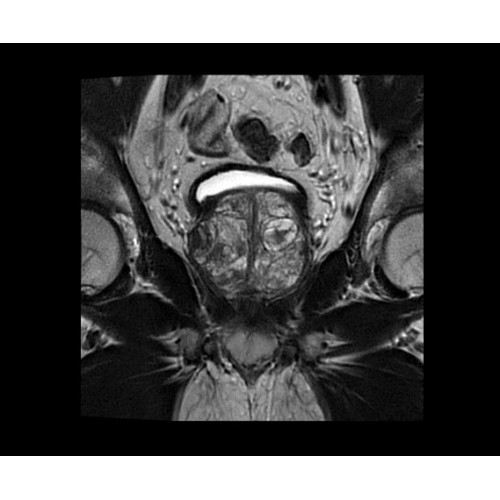

• BodyWorks — для визуализации абдоминальной и тазовой областей, подстраиваясь под запросы пользователя с учетом любых типов пациентов.